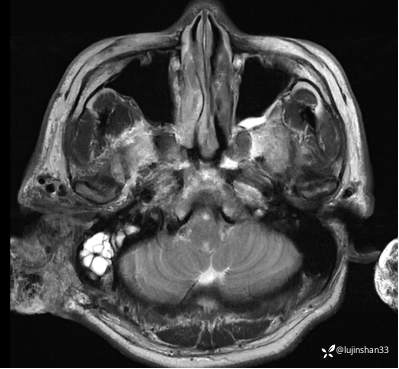

(2023-02-17 17:52,本院)行CT(血管心脏)检查提示:1、右侧耳颞部异常改变,考虑血管瘤可能,可见粗大供血动脉及引流静脉,局部动静脉瘘可能,右侧颈外动脉分支增粗,请结合临床及相关检查。2、左侧颈内动脉粥样硬化,管腔轻微狭窄,请结合临床。血管外科会诊意见:CTA示右颈外动脉起始部结扎后闭塞,介入栓塞暂无合适入路;

临床诊断:耳廓、颞骨蔓状血管瘤合并出血